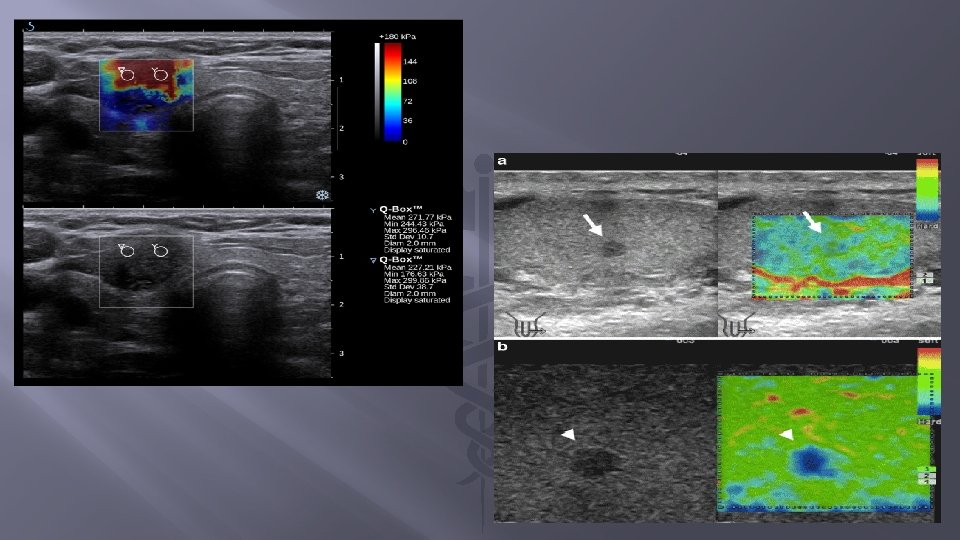

� Elastografie strain realizata prin compresie manuala, (carcinom mamar ductal invaziv).

EVALUAREA ELASTOGRAFIEI STRAIN Se realizeaza prin: - SCORUL UENO sau SCORUL TSUKUBA, - STRAIN RATIO, !!! nu prin determinre cantitativa (exprimata in k. Pa sau m/s);

SCORUL UENO Clasifica in 6 categorii elasticitatea(duritatea) formatiunilor mamare. Scorul se stabileste prin suprapunerea aspectului elastografic al leziunii peste cel din ecografia conventionala – apreciaza distributia elasticitatii in interiorul si in jurul formatiunii mamare identificate ecografic. Semnificatie clinica: Probabilitatea unui cancer mamar creşte o dată cu creşterea scorului UENO. In general, un scor de 1 -3 corespunde cel mai frecvent unei leziuni benigne, în timp ce scorul 4 şi mai ales 5 sugerează prezenţa unei tumori maligne.

STRAIN RATIO Reprezinta raportul dintre elasticitatea leziunii şi elasticitatea ţesutului mamar normal adiacent. În general, un raport ≥ 5 ridică suspiciunea unui cancer mamar

SW-realizata cu un echipament GE - se observa ca sau facut 9 determinari in doua regiuni de interes Q-box 1 si Q-box 2 calculinduse ulterior media duritatii hepatice in esantionul studiat.

SSI(Supersonic Share Imaging) � � � Una din cele mai avansate metode de elastografie ce creaza o harta 2 D, color, in timp real, a elasticitatii unui tesut. Are implementate doua inovatii: prima ar fi faptul ca foloseste simultan mai multe push-uri invecinate iar a doua, consta in viteza foarte mare de procesare a imaginii (peste 10. 000 cadre/s). Este deasemeni o metoda cantitativa, utilizata in elastografia de inalta rezolutie pentru sin, tiroida, ficat, prostata, testicol, musculoscheletal etc.

Imagine Supersonic shear-wave: � (A) - albastru inchis reprezinta tesutul hepatic normal; si � (B) - imaginea unui ficat cirotic-albastru-verzui deschis. Q-box reprezinta zona pe care s-a calculat media duritatii tesutului hepatic.